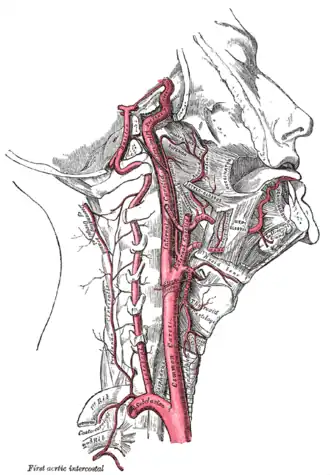

Виллизиев круг Внутренняя сонная и позвоночные артерии (правая сторона)

Внутренняя сонная и позвоночные артерии (правая сторона) Продолговатый мозг и мост. Передняя поверхность.